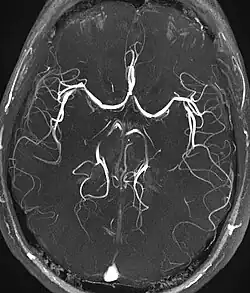

Magnetresonanzangiographie

Die Magnetresonanzangiographie (MR-Angiographie, MRA) ist ein bildgebendes Verfahren zur diagnostischen Darstellung von Blutgefäßen (Arterien und Venen) mit den Methoden der Magnetresonanztomographie (MRT). Zu diesem Zweck können unterschiedliche Techniken eingesetzt werden, die zum Teil vollständig nicht-invasiv sind (also ohne operative Eingriffe und Injektionen auskommen) oder auf der Gabe von MRT-Kontrastmittel basieren. Im Gegensatz zur konventionellen Angiographie werden anstelle von zweidimensionalen Projektionsbildern bei der MRA im Regelfall dreidimensionale Datensätze aufgenommen, die eine Beurteilung der Gefäße aus allen Blickrichtungen ermöglichen. Ein weiterer Unterschied zur konventionellen Angiographie ist, dass bei der MRA kein Katheter in das Blutgefäßsystem eingeführt werden muss. In vielen Bereichen ist die MRA ein zu digitaler Subtraktionsangiographie, CT-Angiographie und Sonographie konkurrierendes Verfahren.[1][2]

Time-of-Flight-MRA

Die Time-of-Flight-MRA (TOF-MRA) nutzt aus, dass frisch einströmendes Blut im Untersuchungsvolumen eine höhere Magnetisierung aufweist, als das stationäre Gewebe, dessen Magnetisierung durch die einwirkenden HF-Pulse der MRT-Pulssequenz reduziert (gesättigt) wird. Die Blutgefäße mit frisch einströmendem Blut werden daher signalreich dargestellt. Für die TOF-MRA werden gewöhnlich schnelle 2D- oder 3D-Gradientenecho-Techniken (FLASH) eingesetzt; es wird kein Kontrastmittel benötigt.